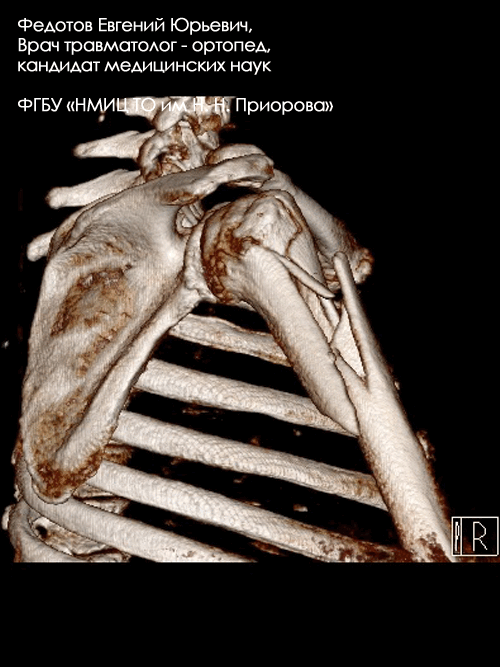

Переломы верхнего отдела плеча (проксимального отдела плечевой кости).

Такие переломы при некорректном лечении могут привести к выраженным нарушениям движений в плечевом суставе, когда пациент элементарно не может достать рукой до головы. Оперативное лечение таких переломов сложно и требует высокой квалификации хирурга и применения современных методик. При соблюдении этих условий в настоящее время можно достичь практически полного восстановления функции плечевого сустава.

Пациентка с тяжелым переломом верхнего отдела (хирургической шейки) плечевой кости.

Рентгенограмма до операции.

Пациентка с очень тяжелым переломом верхнего отдела плечевой кости со значительным смещением отломков.

Пациентка с оскольчатым переломом верхнего отдела плечевой кости.